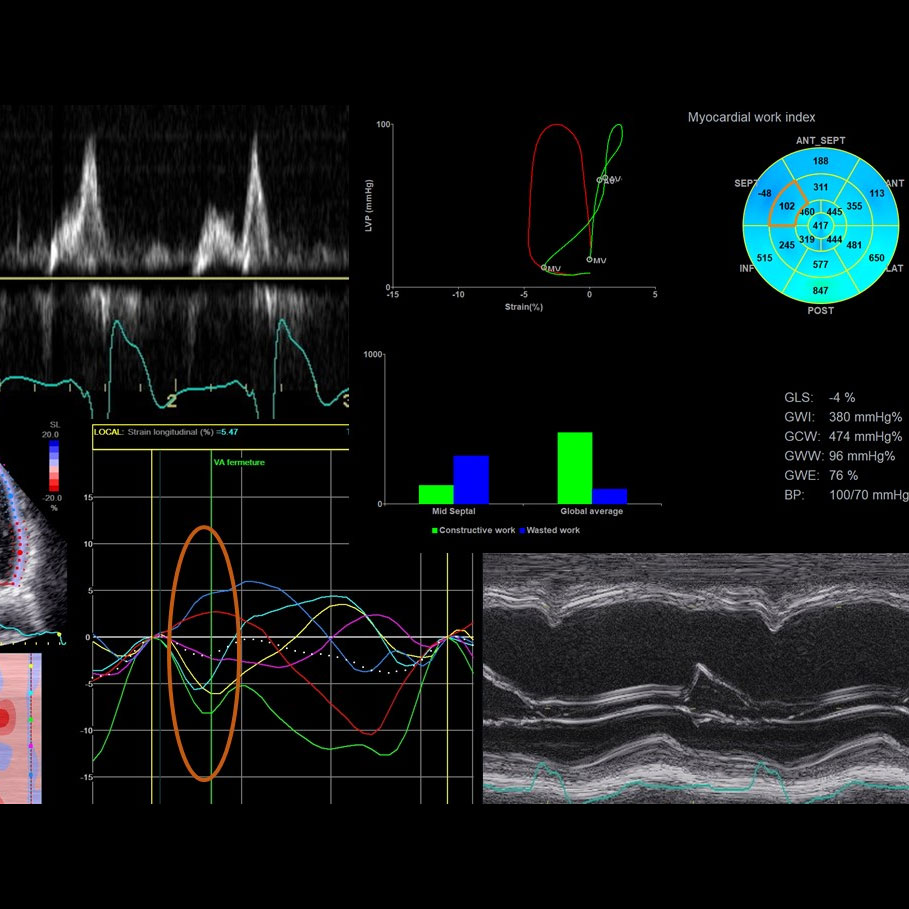

CRT image